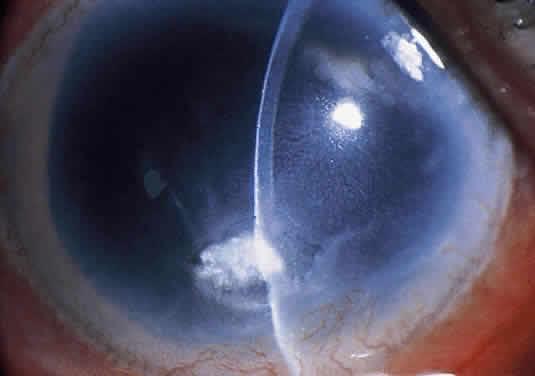

It is important to asses the severity of the microbial keratitis at the initial examination to determine whether hospitalization is indicated and the relative level of antibiotic therapy that may be required. Using a modification of Jones's grading for the severity of microbial keratitis (Figs. 16 to 18),9 the following general guidelines are offered (Table 4).

Fig. 16. Nonaxial, small anterior stromal corneal infiltrate with minimal anterior chamber reaction.

Fig. 17. Central, moderately sized corneal ulcer involving the mid stroma and producing a significant anterior chamber reaction.

Fig. 18. Large, necrotic-appearing corneal ulcer extending into the deep stroma and causing severe anterior segment inflammation.